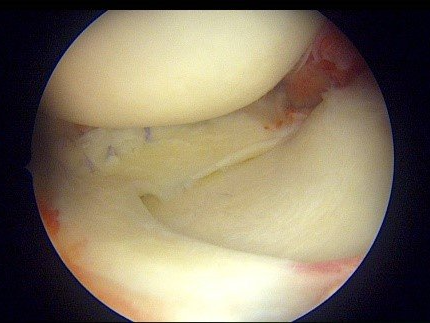

- Réparation méniscale sous arthroscopie : la suture méniscale est proposée chez des patients plutôt jeunes, actifs ou sportifs lorsque la fissure est située en zone favorable (rouge-rouge ou rouge blanc). La suture méniscale est un moyen de prévention de la survenue d’arthrose. En réparant le ménisque, celui-ci va reprendre son rôle d’amortisseur antichoc et de guide du genou. Toutefois, il faut soigneusement sélectionner les patients candidats, car les suites postopératoires sont plus contraignantes. D'abord, marche en appui « soulagé » à l’aide de béquilles pendant 3 semaines. La marche en plein appui sera reprise par la suite. La reprise du sport est attendue au 3e mois postopératoire.

- Méniscectomie partielle sous arthroscopie : lorsque le ménisque est douloureux, mais que la suture n’est pas envisageable, chez des patients peu demandeurs sur le plan sportif ou plus âgés, on proposera une chirurgie d’ablation partielle la plus économe possible de la zone malade du ménisque. Cette technique a l’avantage de permettre un retour rapide aux activités (marche en plein appui dès la sortie de la clinique le jour même) et une reprise du travail accélérée. Toutefois, le risque d’arthrose est majoré. Il faut cependant nuancer un point. Ce n’est pas la méniscectomie qui aggrave le risque d’arthrose, mais le fait que le ménisque lésé ne remplit plus son rôle d’amortisseur. La méniscectomie économe doit être effectuée par un chirurgien entraîné pour ne pas être excessive.